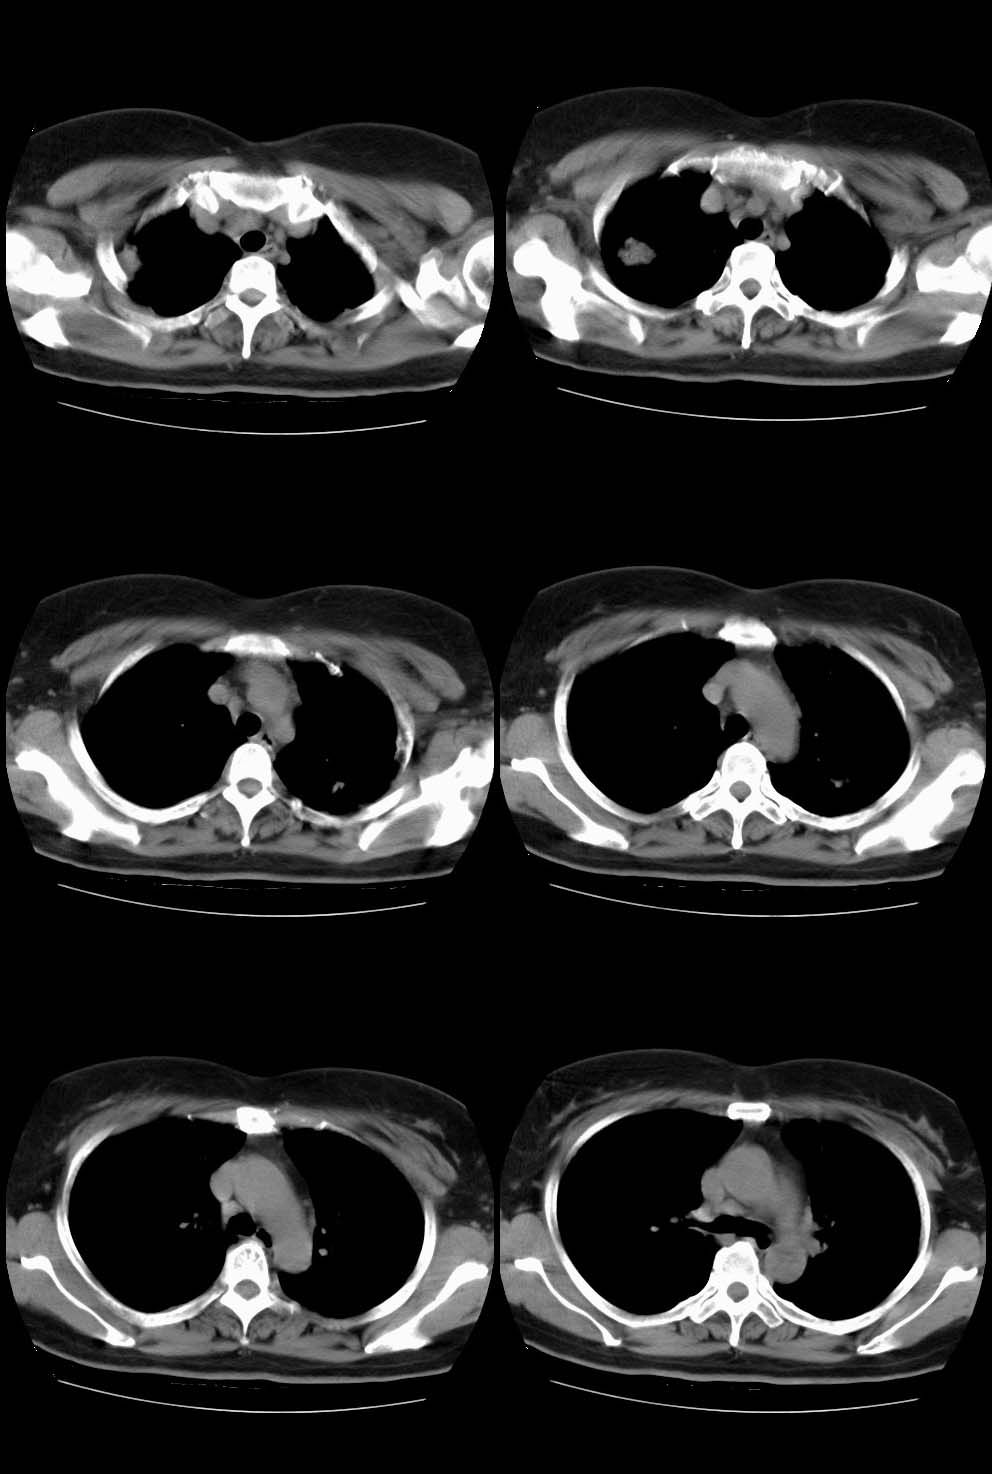

女,64岁,2月前体检透视发现右上肺阴影,未行任何治疗。无咳嗽咳痰、胸痛胸闷症状。生化检查(血象、防癌全套等)均未示异常。轻—中度强化。

见点状钙化的卫星灶,左上肺也有点状钙化灶。

右肺上叶结核瘤。

右上肺占位考虑结核球,左上肺病灶有钙化,考虑慢性炎变,所以双肺改变考虑结核

右上病变有脂肪及钙化,考虑良性病变,错构瘤可能性大,左上陈旧性tb。

右肺上叶肿块,边缘毛糙,未见钙化,考虑周围型肺癌,左肺斑点状及索条状高密度,考虑结核。

肿块内有钙化,虽无明确卫星病灶,还是考虑结核球可能大,随访除外新生物。

另左上肺纤维硬结灶。

右上肺结节有分叶征、但似可见细小的沙粒状钙化阴影,邻近胸膜有增厚而不是胸膜凹陷证。结节有轻中度强化。这些都是矛盾的。

拟诊:瘢痕ca可能性大。